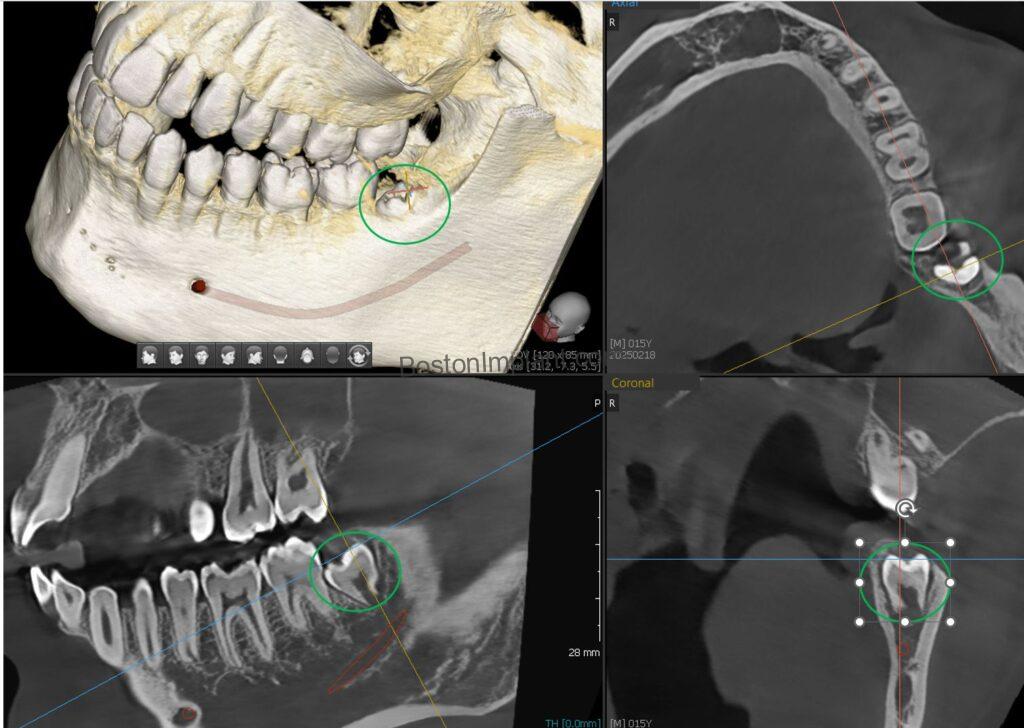

1. Planning Dental Implants: By analyzing bone shape in a three-dimensional view, we can find the optimal position and angle for dental implants. After planning, we create a surgical guide to accurately transfer the plan to the actual surgery. (Please check out our information on dental implant surgical guides!)

2. Endodontics (Root Canal Treatment): CBCT allows for a more thorough evaluation of endodontic issues, such as periapical lesions, which are difficult to assess with regular X-rays. It also helps us evaluate healing after successful root canal treatment.*

5. Wisdom Teeth Assessment: Many wisdom teeth are impacted, and it’s often difficult to predict their exact shape and their relationship to the inferior alveolar nerve using traditional x-rays. Three-dimensional CBCT imaging provides the surgeon with the precise relationship, leading to more accurate diagnoses and safer treatment.